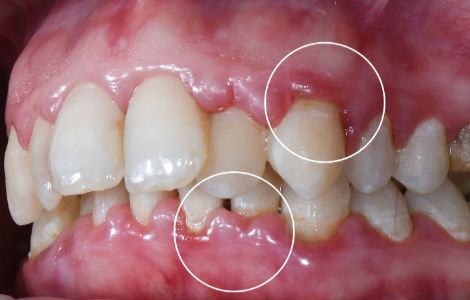

Винирами называют небольшие пластинки из керамики или композитных материалов, которые крепятся к внешней стороне зубов, корректируют их форму и цвет. Преимущественно их устанавливают на фронтальные зубы при эстетических отклонениях: естественная желтизна, пятнистость, искривление, большие зазоры, нарушение формы. Накладки устанавливают только на здоровые зубы.